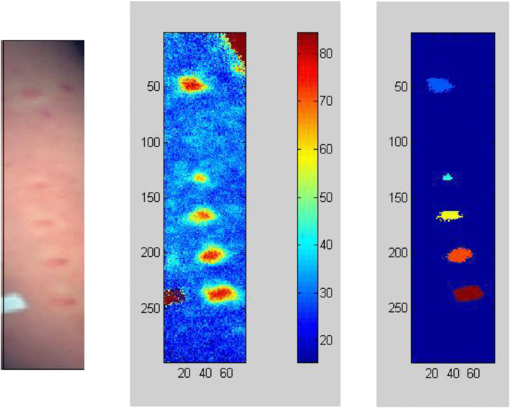

3.3. Photoacoustic tomography